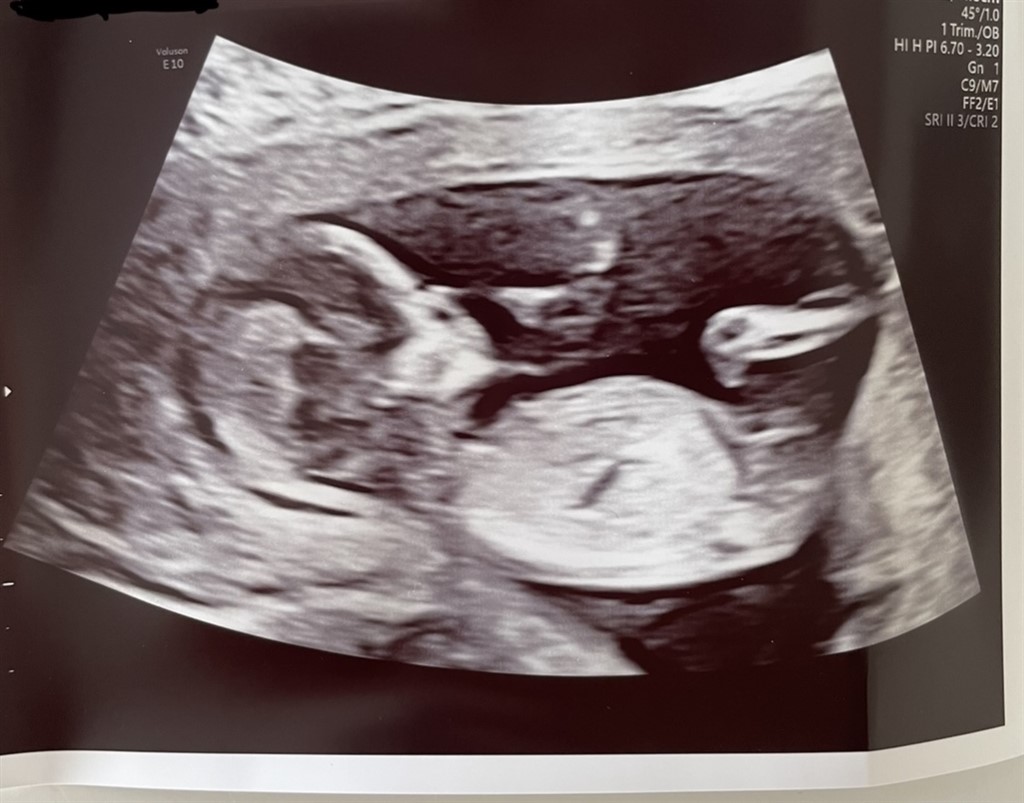

har været til vellykket NF scanning idag og 13+0  Jeg er så nysgerrig på køn, kan nærmest ikke vente de halvanden uge på en kønsscanning.

Er der nogen som er stærke i nub for jeg kan intet tyde ?

Vedhæftede fotos (klik for at se i fuld størrelse)

Næsten 100 procent sikker på det er en dreng

Jeg vil uden tvivl sige en pige.

Jeg vil heller ikke turde gætte på kønnet, synes ikke helt at nubben er så tydelig

Nå.. til vores store overraskelse venter vi os en lille aktiv dreng